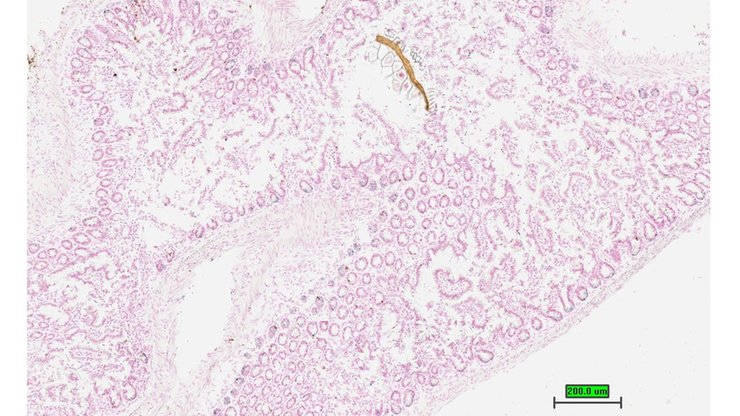

TS28: ileum Present UC Davis_1862811

Specimen UC Davis_1862812: postnatal adult; Ctdspltm1.1(KOMP)Mbp/Ctdspl+ (more )

Structure Level Pattern Image Note

TS28: ileum Present UC Davis_1862812

Specimen UC Davis_1862813: postnatal adult; Ctdspltm1.1(KOMP)Mbp/Ctdspl+ (more )

TS28: ileum Present UC Davis_1862813

Specimen UC Davis_1862814: postnatal adult; Ctdspltm1.1(KOMP)Mbp/Ctdspl+ (more )

TS28: ileum Present UC Davis_1862814